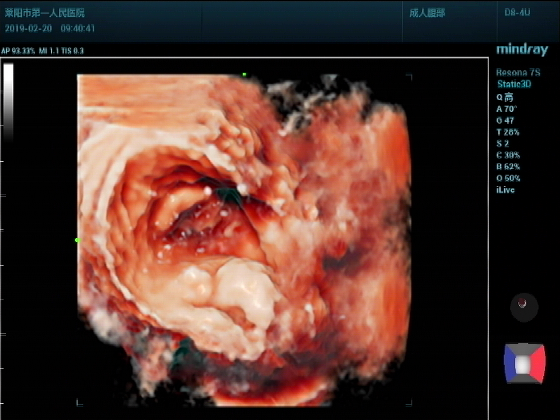

超声入门贴987--前列腺增大并膀胱结石(三维图)

男,75岁超声可见:前列腺明显增大,以内腺增大为主,内腺向膀胱内突入约2.17CM.实质回声尚均匀。膀胱腔内见弧线状强回声团,后伴声影,位置活动。

三维成像:前列腺向膀胱腔内呈“唇样“隆起,表面光滑。膀胱腔内结石团呈”蚕豆样“